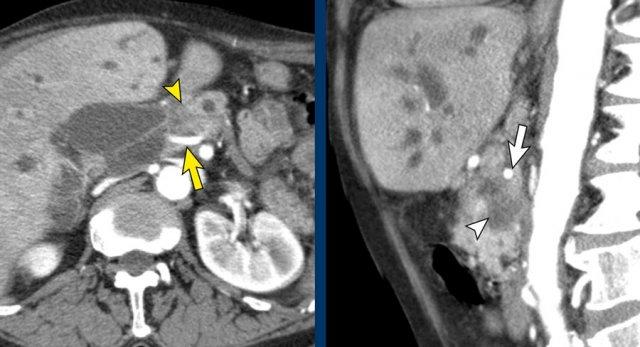

Bất thường bờ viền mạch máu

CT axial cho thấy:

- Khối u ở thân tụy (đầu mũi tên trắng).

- Tiếp xúc khu trú < 90º với động mạch mạc treo tràng trên (SMA).

- Tiếp xúc rộng hơn từ 90º – 180º với SMV, SMV bị hẹp nhẹ và biến dạng (mũi tên vàng).

- Giãn ống tụy

Tái tạo mặt phẳng coronal cho thấy:

- Bất thường bờ viền thành SMV được nhận thấy rõ hơn trên tái tạo coronal này (mũi tên).

- Huyết khối trong các nhánh bên của SMV (mũi tên xanh nhỏ).